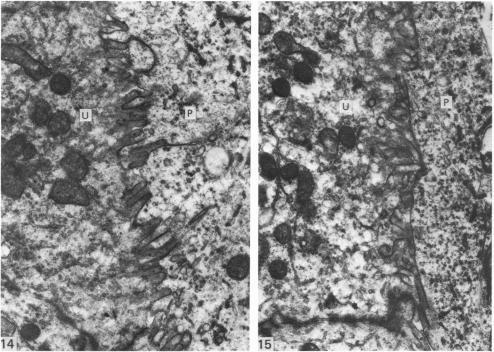

Structure of trophoblast papillae on the sheep conceptus at implantation.

A study of 13-18 days old sheep conceptuses has consistently demonstrated the presence of multicellular protrusions (papillae) from the trophectoderm surface. These papillae were shown to be restricted to the embryonic region of conceptuses flushed out of the uterus. After perfusion fixation of the uterus on day 16 of pregnancy, the papillae can be observed penetrating well down into the lumina of the uterine glands. The papillae have not been observed at or after day 20. It is suggested that the papillae may play an important but transient role in anchoring the embryonic region of the conceptus against the uterine epithelium to allow the initiation of the cellular changes characteristic of implantation.